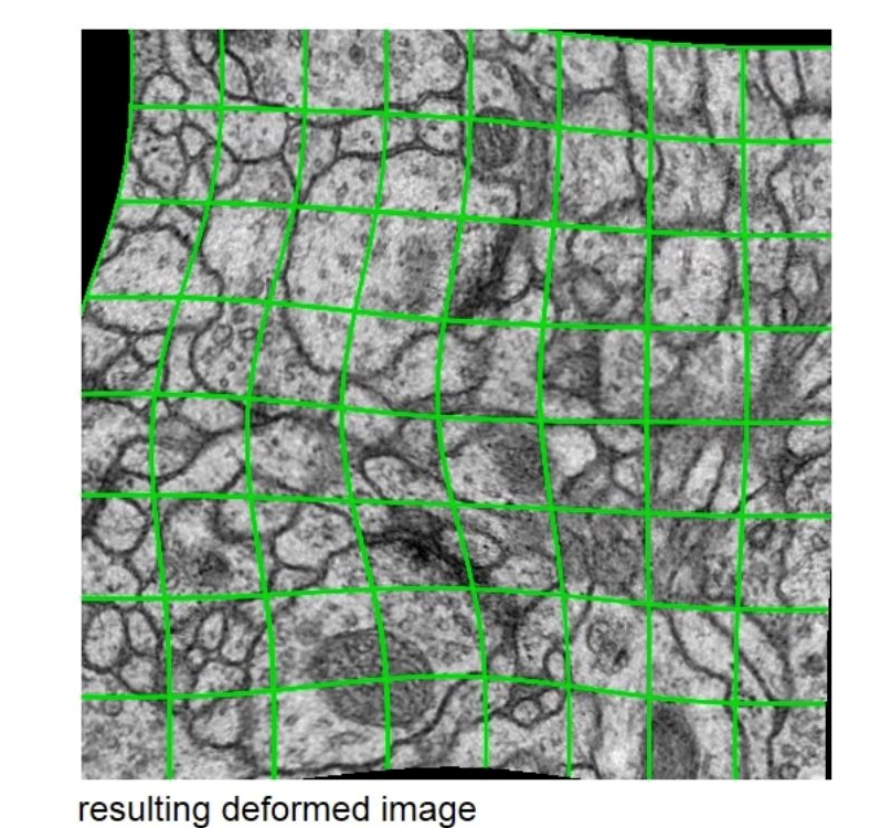

- 1、平移与旋转不变性,并且对形变和灰度变化鲁棒

- 2、将训练样本进行随机弹性形变是训练分割网络的关键

- 使用随机位移矢量在粗糙的3x3网格上(random displacement vectors on a coarse 3 by 3 grid)产生平滑形变(smooth deformations)。

- 位移是从10像素标准偏差的高斯分布中采样的。然后使用bic插值计算每个像素的位移。在contracting path的末尾采用drop-out 层更进一步增加数据(bilinear与bicubic 插值图像处理介绍)

- 位移是从10像素标准偏差的高斯分布中采样的。然后使用bic插值计算每个像素的位移。在contracting path的末尾采用drop-out 层更进一步增加数据(bilinear与bicubic 插值图像处理介绍)

- 使用随机位移矢量在粗糙的3x3网格上(random displacement vectors on a coarse 3 by 3 grid)产生平滑形变(smooth deformations)。